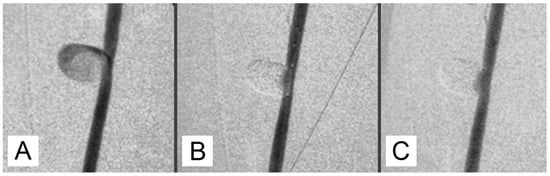

After 30 min of packaging, there was no migration or leakage of GEL. Post-procedure angiographic controls showed a stable occlusion of all the aneurysms with no signs of recurrence (Figure 2A,B).

3.2. Macroscopic Study

Figure 2. (A) An angiographic intraoperative control after embolization with balloon deflated. (B) Follow-up control at 90 days. Occlusion remains stable. (C) Aneurysms excised.